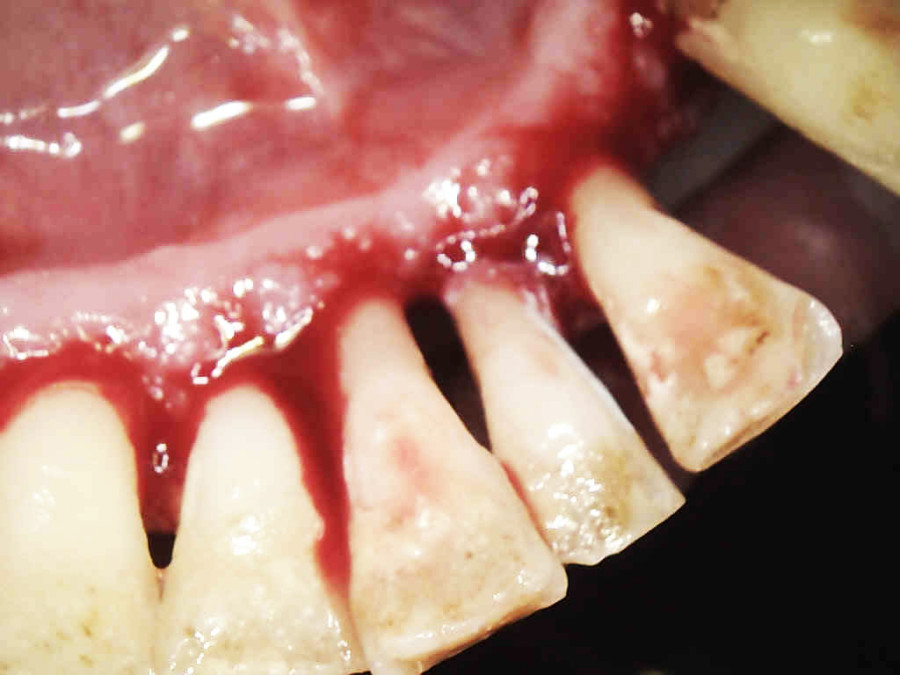

Postępowanie rozdzielono na dwie wizyty. Badaniem klinicznym, oceniając wskaźniki periodontologiczne, uzyskano wartości API 100%, PBI 100% świadczące o konieczności poprawy higieny i procesie zapalnym dziąseł, duże złogi kamienia nad i poddziąsłowego, bardzo obfity biofilm, pogłębione wszystkie kieszonki dziąsłowe, ciężkie zapalenie dziąseł, ruchomości zębów dolnych III stopnia, duży zanik kości. Badanie kliniczne błony śluzowej jamy ustnej nie wykazało zmian patologicznych.

Na pierwszej wizycie usunięto złogi kamienia nad- i poddziąsłowego za pomocą skalera ultradźwiękowego EMS oraz osady i biofilm za pomocą piaskarki airflow S2 EMS –użyto piasku AIR-Flow PLUS. Ponieważ pani jest bardzo wrażliwą osobą, a stan zapalny dziąseł był bardzo duży, pacjentka została miejscowo znieczulona do zabiegu.